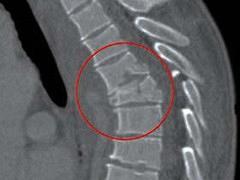

Specifieke aandoeningen aan de wervelkolom Lees meer over Specifieke aandoeningen aan de wervelkolom Specifieke aandoeningen aan de wervelkolom

Rugpijn is een veelvoorkomend probleem in onze maatschappij. Bij deze patiëntengroep is het van belang om als eerste stap specifieke rugklachten (klachten met een definieerbare oorzaak) te onderscheiden van aspecifieke rugklachten (klachten zonder definieerbare oorzaak). De rode vlaggen bieden hiervoor aanknopingspunten en bij de aanwezigheid van rode vlaggen dient een verwijzing plaats te vinden naar de tweede lijn. Het is van belang dat alle disciplines dezelfde alarmsignalen gebruiken en het belang daarvan inzien. Om een brug te slaan tussen eerste en tweede lijn geeft dit artikel geeft een overzicht van de pathofysiologie, diagnostiek en het klinisch beeld van de meest voorkomende wervelkolomaandoeningen.